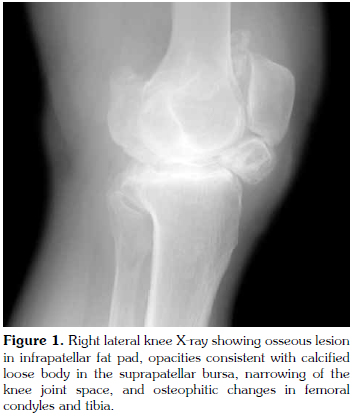

In the physical examination, the patient had an incision scar on the right knee. A difference of 5 cm was found in the right calf compared to the left calf. The right quadriceps muscle had an atrophic appearance. Palpation revealed no effusion. Active flexion of the right knee joint was limited to 110 degrees, and the end of the movement was painful. The right knee joint was capable of full active extension. Bilateral crepitations were present. Anteroposterior view of the X-ray scan showed joint space narrowing and coarse osteophytic formations predominately involving the medial compartment (Figure 1). A right lateral radiograph revealed opacity in the suprapatellar region and an ossific focus measuring 2.25 cm on the longitudinal axis and 2.75 cm on the horizontal axis, located in IFP (Figure 2). Magnetic resonance imaging (MRI) of the right knee showed increased fluid in the suprapatellar bursa and joint. There were loose body formations in the suprapatellar bursa and joint, and a smooth contoured lesion that was hypointense to muscle in the IFP (Figure 3). Routine biochemistry tests showed no abnormalities. The erythrocyte sedimentation rate was 43 mm/h, considered normal for the patient's age. Based on her medical history, physical examination and imaging findings, the patient was evaluated to have advanced Hoffa's disease developing secondary to past trauma or surgery, considering also the ossific focus later forming in the IFP region. Orthopedic consultation was requested. Surgery was recommended. However, medical treatment and physical therapy program was initiated for longterm monitoring, as since the patient did not have severe symptoms and did not consent to surgery. In the course of time, the patient's symptoms relieved.